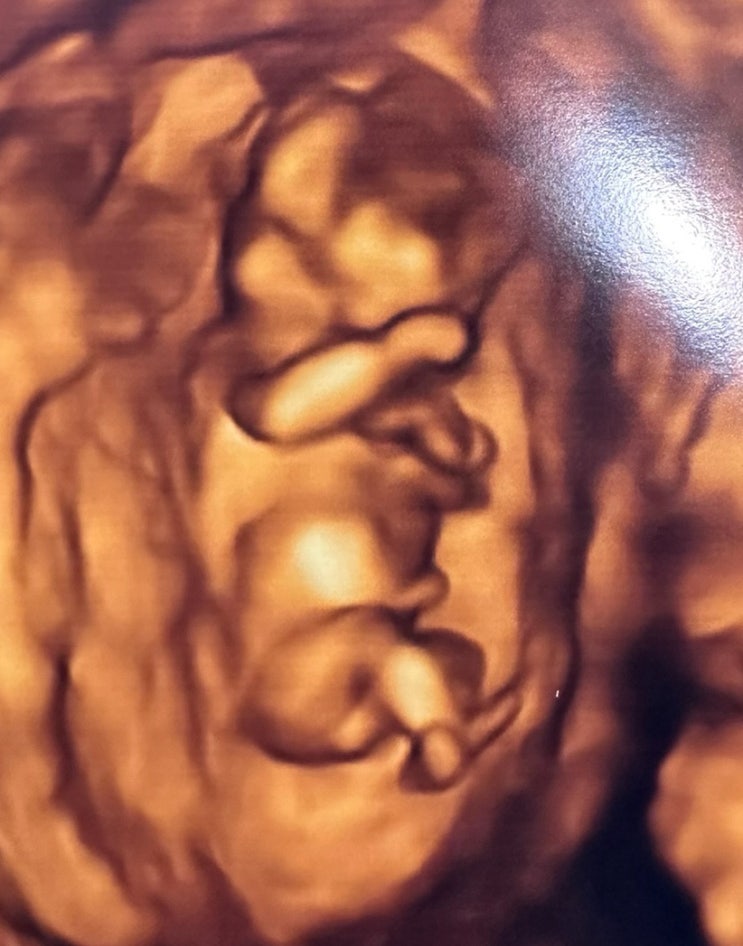

노산 다운증후군 고위험군 1:5 / 임신15주5일 , 16주1일 양수검사실패 / 17주3일 세번째양수검사 시도 / 커피색양수 / 보리차색양수 / 갈색양수

기록. 일단, 바로밑에 쓴 글의 결과는 ~ 바로바로 딸 !! 하지만, 그 기쁨도 잠시. 제발, 건강하기만 해라 -...

아들둘맘의 셋째딸 희망, 각도법 12주1일차 초음파, 임신아들증상 임신딸증상 비교

오죽 궁금하면, 진짜 복직에, 입덧에, 아둘육아에 모든 블로그생활을 내려놨던 내가 올려보는 포스팅 이미 ...